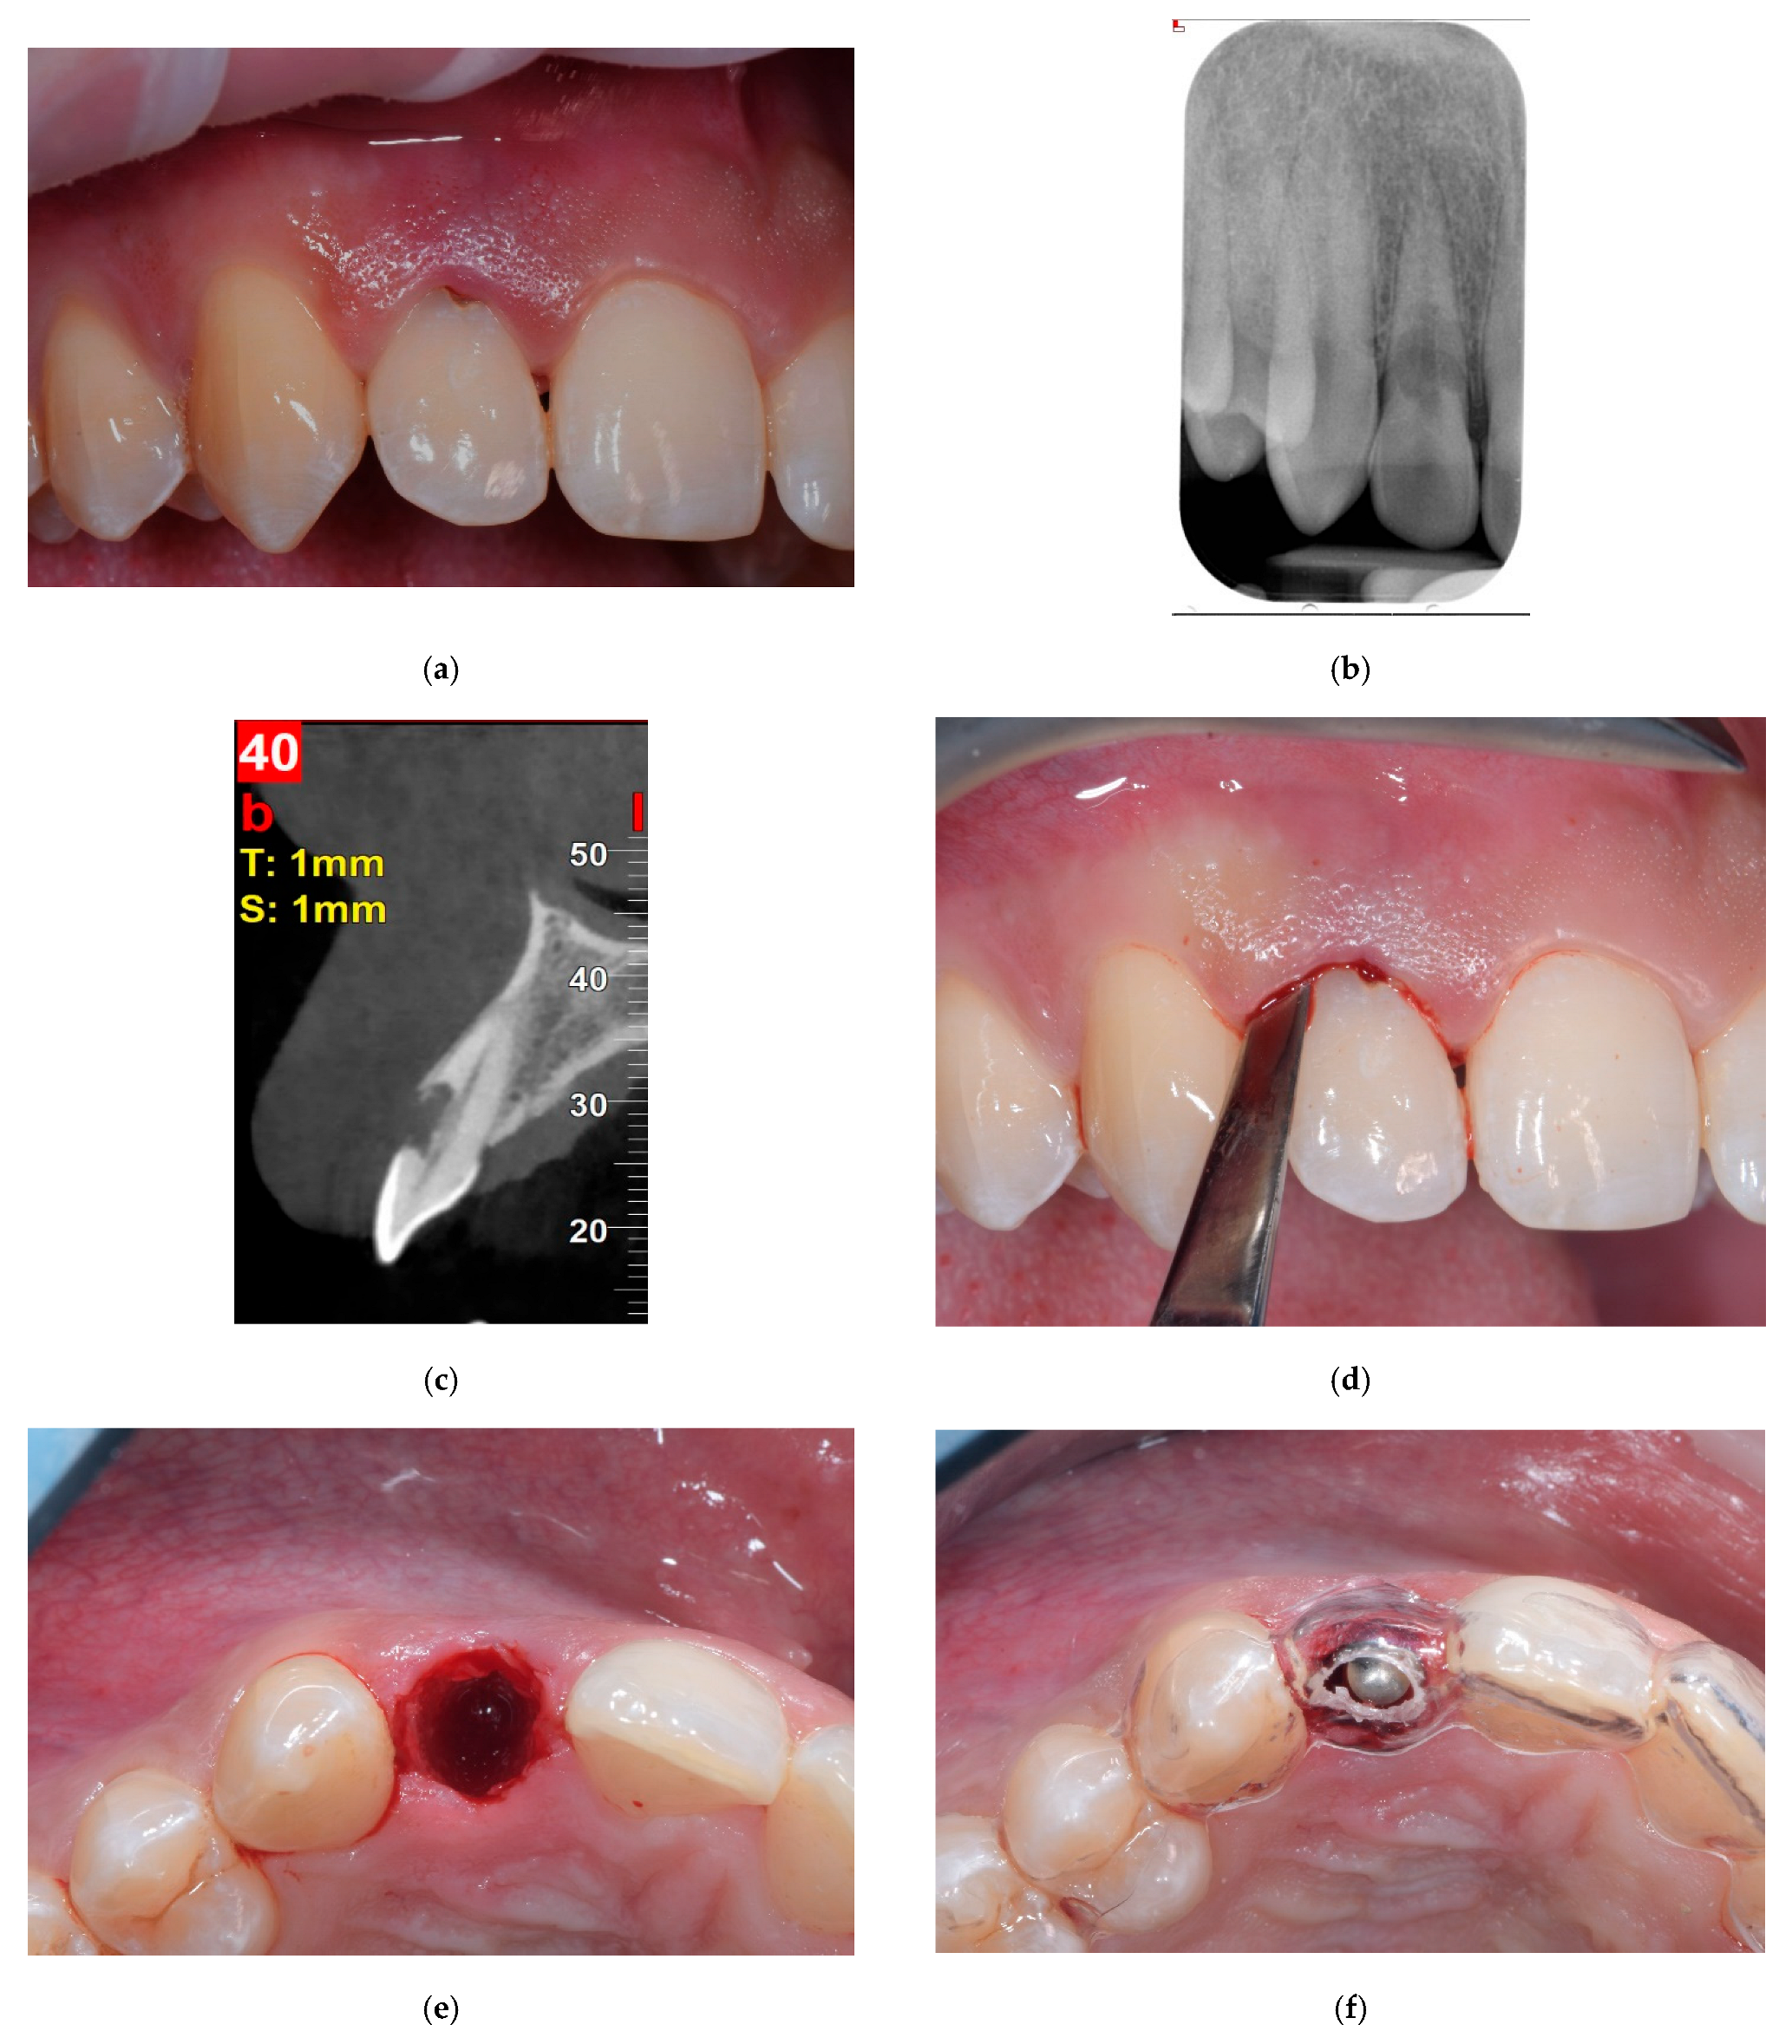

Clinical and Radiological Evaluation of a Fully Tapered Implant Design Following Immediate Placement with Immediate Provisionalization in the Esthetic Area: A Prospective Case Series Study

2. Materials and Methods

3. Results